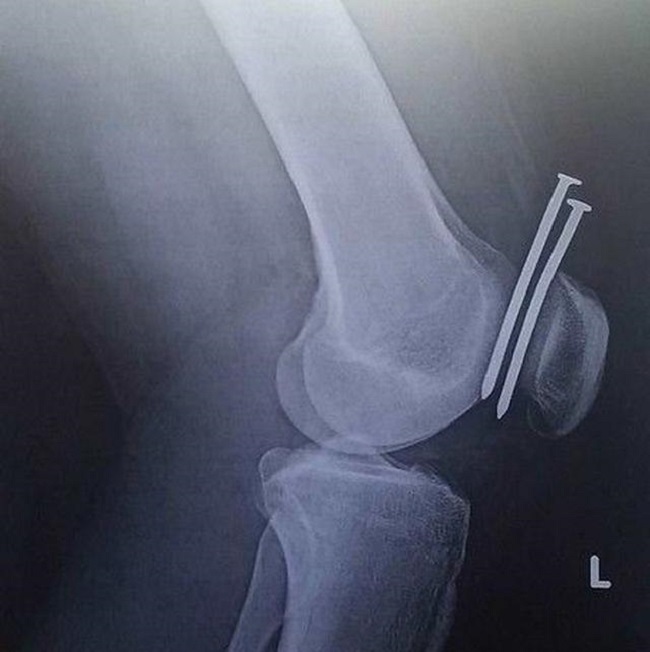

10Accidents do happen

Especially when you are working in construction and it appears that even though this construction worker got two huge nails embedded into him, the lucky fact here is that they don’t penetrate and shatter the bone. A shattered knee isn’t a nice condition.